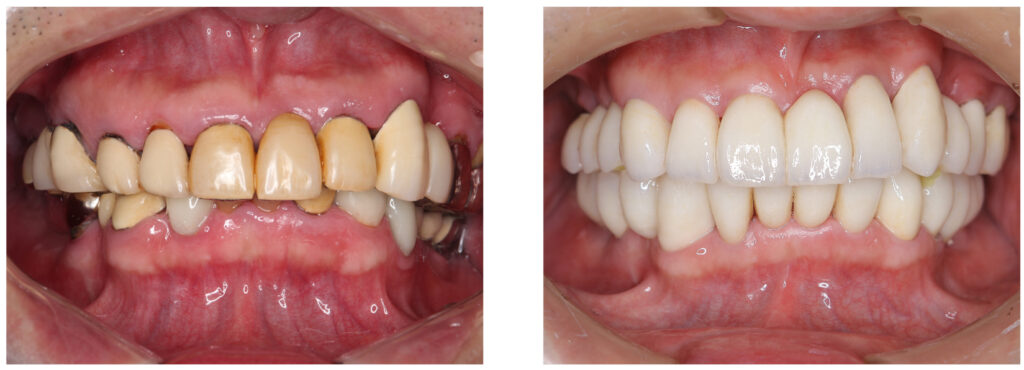

ご自身の大切な歯を失ってしまった場合にはインプラント治療が有効な治療のうちの一つです。当院では精密な歯科治療で歯を削らないように心がけていますが、外傷や歯周病、虫歯などで歯を失ってしまった方には天然の歯とほぼ同等の噛む力を取り戻せるインプラント治療もおすすめしています。

歯を失ってしまっても健やかな生活を送れるように、第2の永久歯ともいわれているインプラント治療で人工歯を装着するサポートを当院でいたします。インプラント治療で不安に感じている方もご安心ください。メリットとデメリットも含めて丁寧にご説明させていただき患者さまに寄り添った治療をしていきます。

インプラントとは、歯が無い顎の骨に人工歯根を埋め込み、それを土台にしてセラミックの歯を装着する治療です。

顎の骨に固定した人工歯根を固定するため、自分の歯のように食事をすることができ、見た目も自然に仕上がるので第2の永久歯とも呼ばれています。従来のブリッジ・入れ歯などの治療法とは違い、歯根も取り戻すことができるのが特徴です。しかし、歯根を埋め込むので手術が必要になるというデメリットもあります。